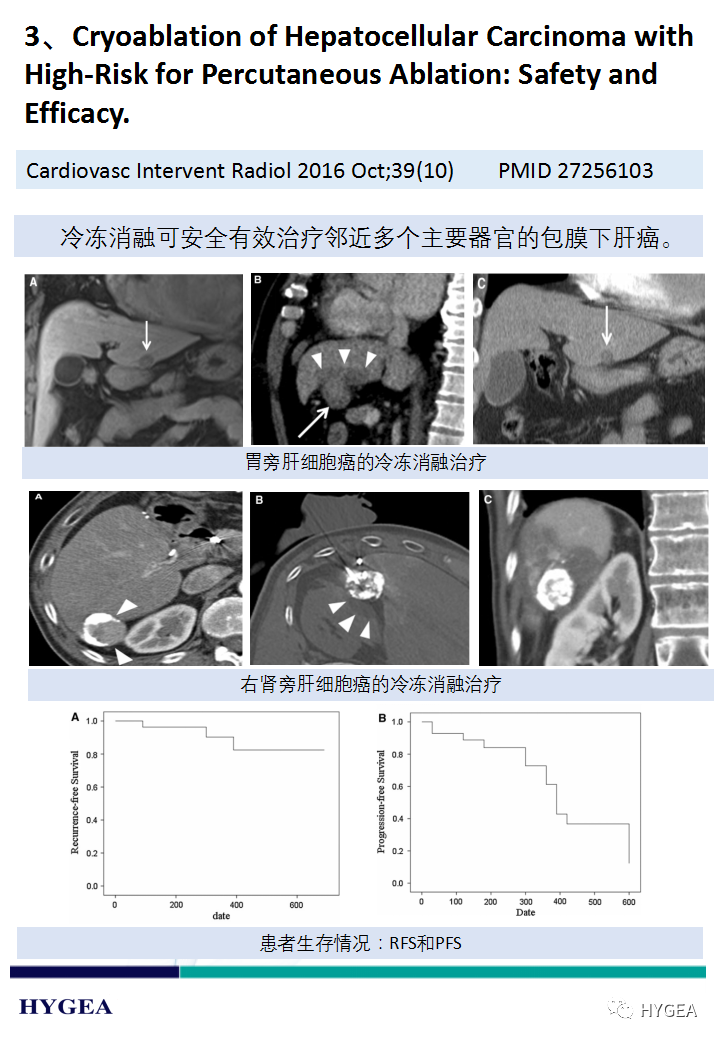

【海杰亞科研資訊】第188期——冷凍消融肝癌專題